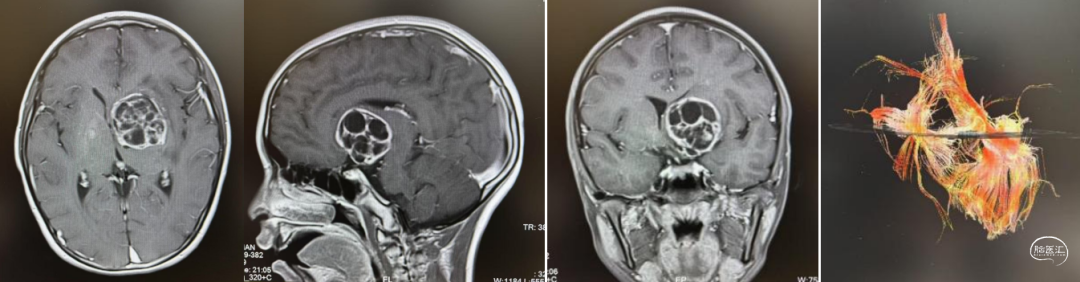

头部CT显示:左侧基底节区囊实性占位性病变,大小约40*36mm,内有多发钙化,低密度区CT值约12HU,临近脑实质密度减低,左侧脑室,邻近中线结构右移。

头部MRI显示:左侧基底节区囊实性肿块,内见实性成分及分隔,呈稍长T1稍长T2信号灶,FLARE呈高信号,大小约47*39*40mm,增强后实性成分及分隔明显强化。右侧侧脑室受压,周围脑实质可见条片状稍长T2水肿带,中线右移。

经纵裂胼胝体入路全切除病变。右侧肢体肌力4级。

病理检查:(左侧基底节)混合性生殖细胞肿瘤(50%生殖细胞瘤+50%胚胎性肿瘤)。免疫组化:CK-Pan(+),CD117(+),D2-40(+),Oct(+),AFP(部分+),PLAP(部分+),CD30(+),HCG(-),EMA(+),SALL4(+),Ki(约70%)。

术后建议辅助治疗。结疗后未见肿瘤复发,肌力已恢复至5-级。此后2年予以定期复查未见复发。

术后2年(已完成放疗化疗)